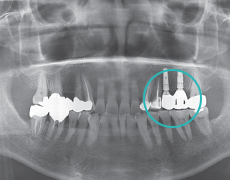

Étape 4

Installation de prothèseUne dent artificielle est installée sur l'implant pour compléter le traitement.